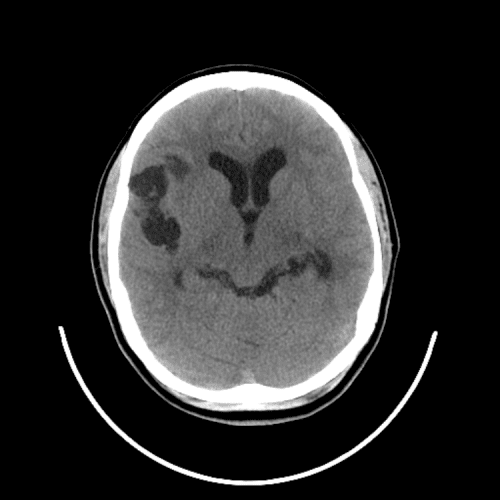

PICA infarct